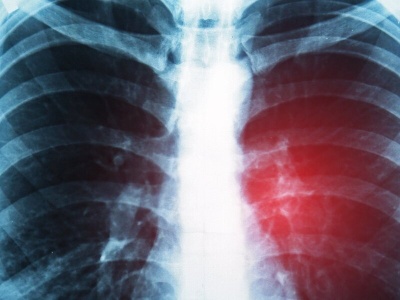

Rak drobnokomórkowy płuca przez lata uchodził za nowotwór bez skutecznego leczenia. – To najbardziej agresywna postać raka płuca, ale dziś mamy terapię, która niemal dwukrotnie wydłuża życie pacjentów – mówi prof. Damian Tworek, onkolog kliniczny, podkreślając znaczenie szybkiej diagnostyki i Lung C...